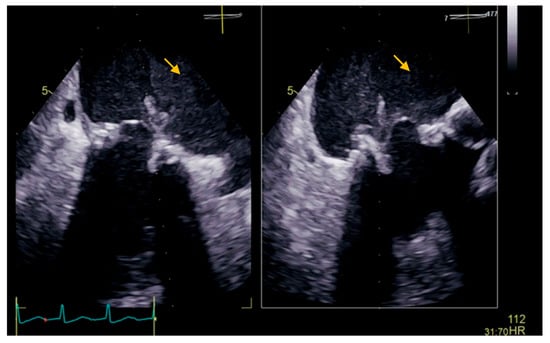

:1. Case Presentation